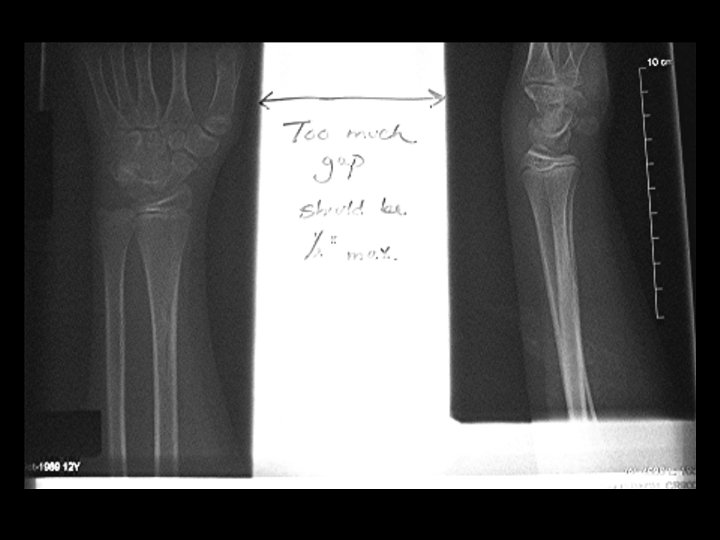

Exposure Numbers n The exposure numbers can only be used if all other parameters are correct ¨ Centering to plate ¨ Collimation n Position over AEC, look at m. As readout to determine if poor positioning caused light or dark image

Same technique, different centering and collimation S# 592 S# 664

�� 2 on 24 X 30 �� Technique adjusted 2 on 24 X 30 �� Same technique �� Rescaling error.